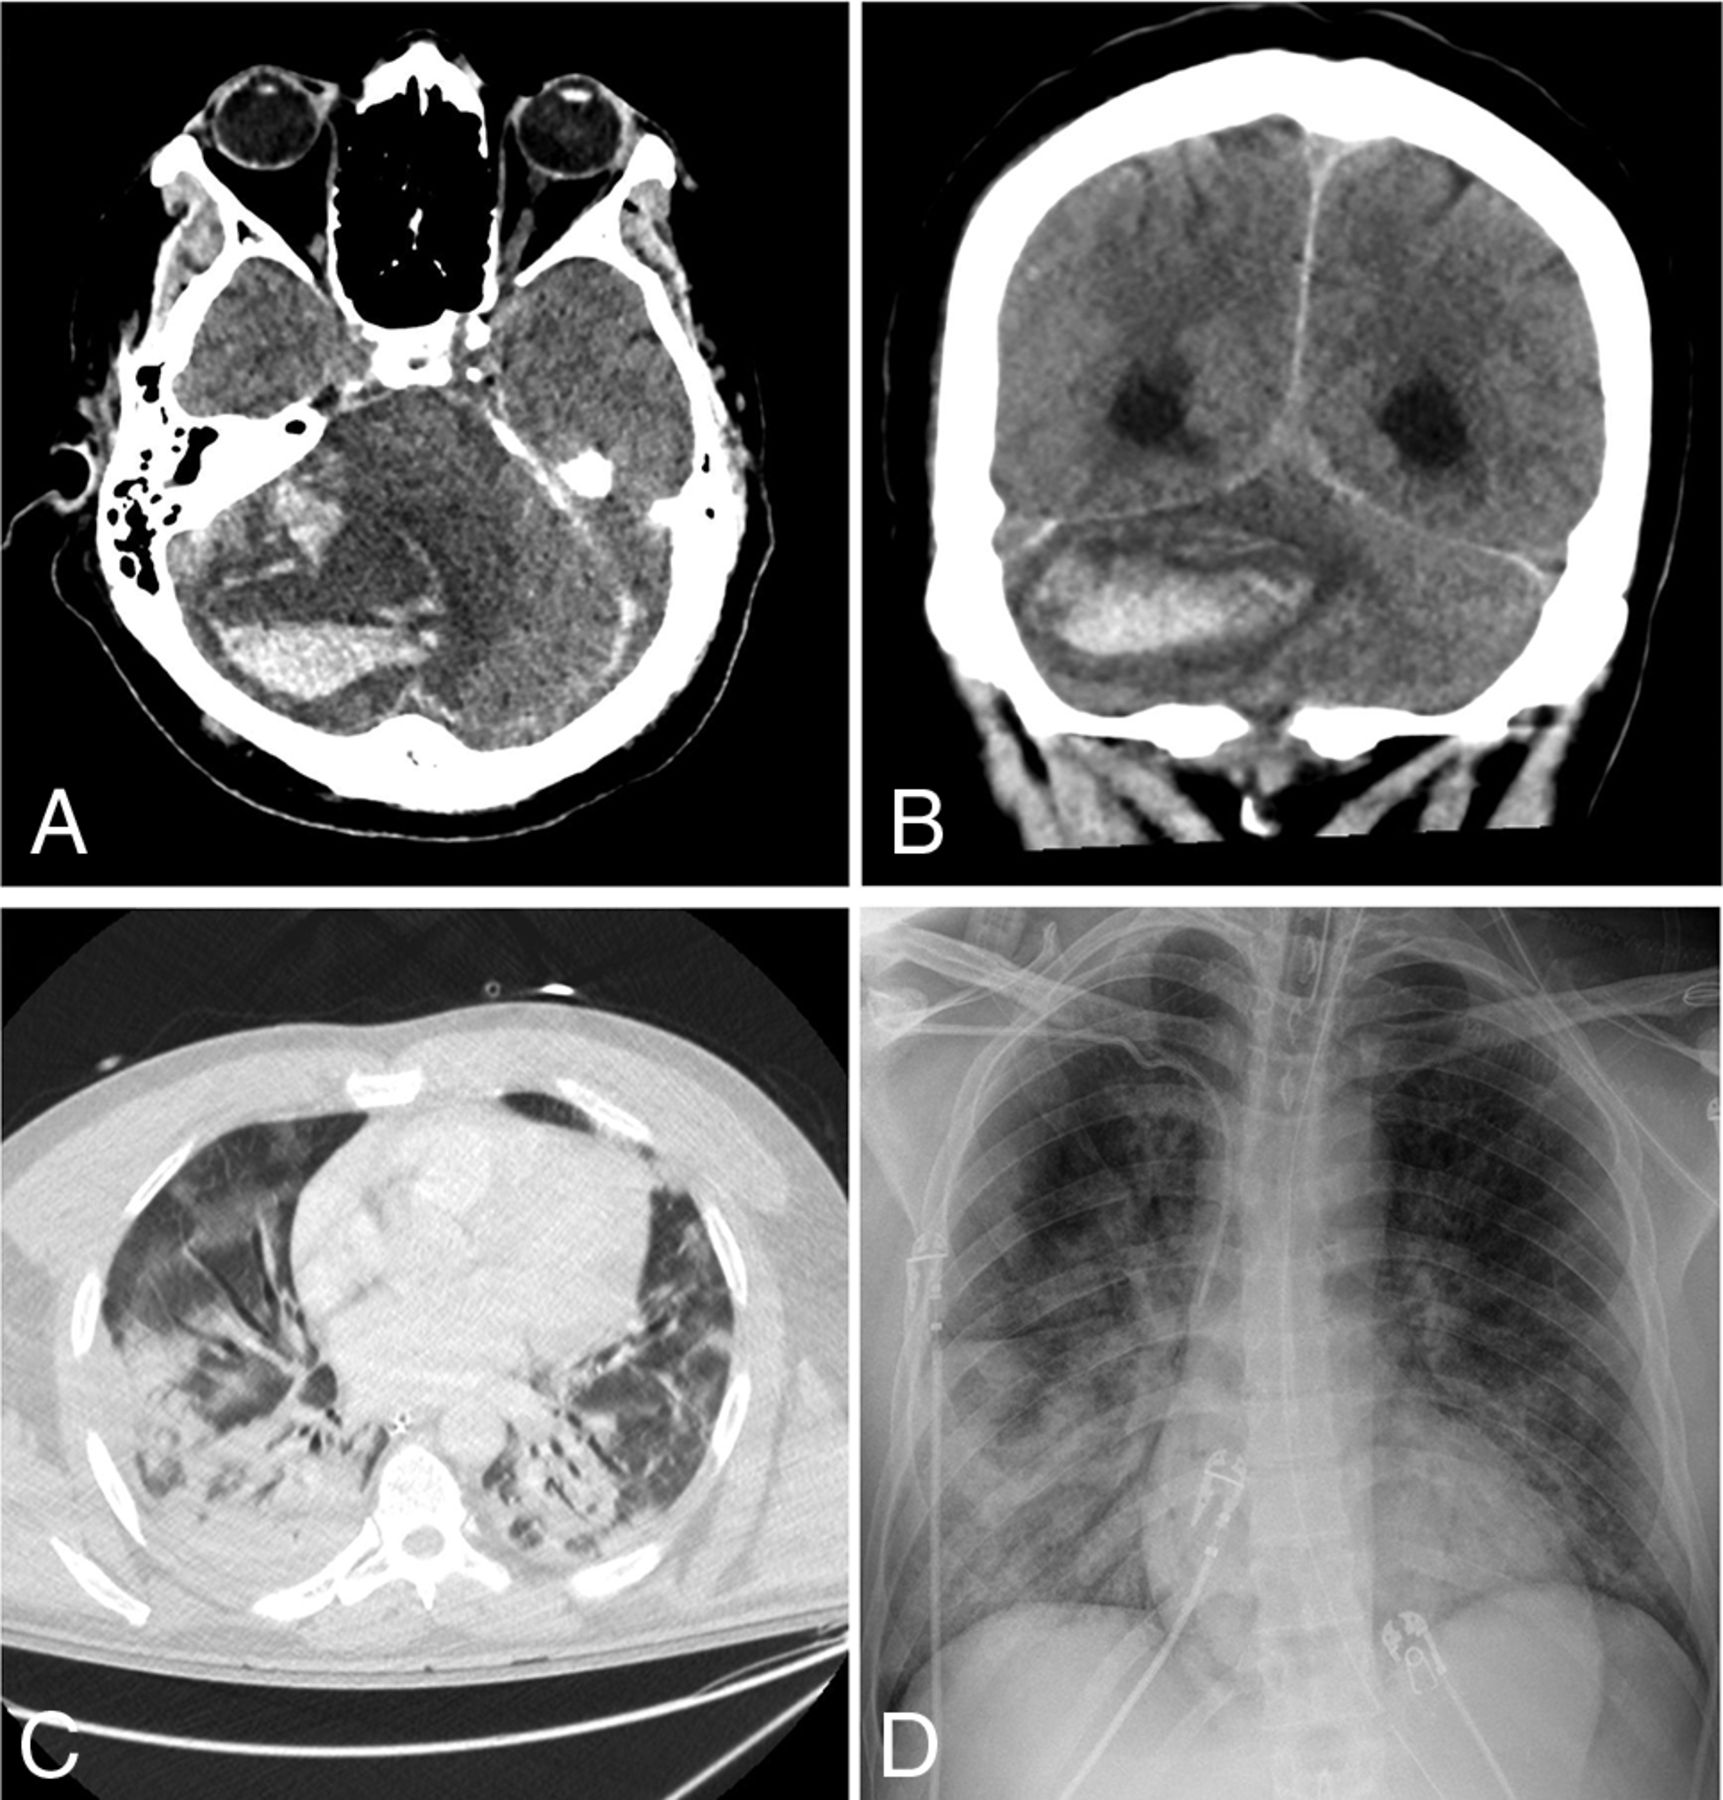

Of the 24 patients with acute neuroimaging findings, 7 patients were found to have intracranial hemorrhage (Fig 1), 7 patients were found to have acute infarction (Fig 2), 6 patients were found to have leukoencephalopathy (Fig 3), 3 patients had intracranial hemorrhage and infarction, and 1 patient had intracranial hemorrhage, infarction, and leukoencephalopathy (Table 2). Sixty-nine patients did not have acute neuroimaging findings (Fig 4). There was no significant difference (P = .225) between the distribution of Radiological Society of North America categories of chest CT findings between patients without acute neuroimaging findings (n = 66) and those with acute neuroimaging findings (n = 14), with the “typical” category being the most prevalent in both groups (Table 2).21

A 42-year-old man presented with hypoxemic respiratory failure. Non-contrast-enhanced axial (A) and coronal (B) CT head images demonstrate a new, large, right cerebellar intraparenchymal mixed-attenuation hematoma suggestive of hyperacute or active hemorrhage. C, Chest CT of the patient demonstrates bilateral consolidation and ground-glass opacities involving all lobes, with a CCS score of 18. D, Portable chest radiograph demonstrates bilateral patchy air space opacities with a PXS score of 10.3.